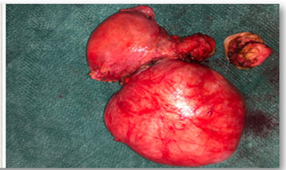

Transvaginal ultrasound showed a 11x10x9 cm uterine tumour suggestive of subserous myoma FIGO 7, located in the left lateral fundus of the uterus (Figure 1). Reviewing her medical history, we found a computed tomography scan 5 years earlier with a 4 cm uterine fibroid in the same location (Figure 2).

Figure 1 5 months before CT abdominal: Uterine posterior myoma of 40 mm.

Figure 2 Current pelvic ultrasound. Uterine myoma of 110 mm.